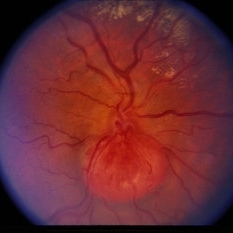

Retinal Capillary Hemangioblastoma

Retinal capillary hemangioblastoma associated with Von Hippel-Lindau Disease. No history. Dilated tortuous vessel and hemorrhage is shown.

Condition/keywords: retinal capillary hemangioblastoma